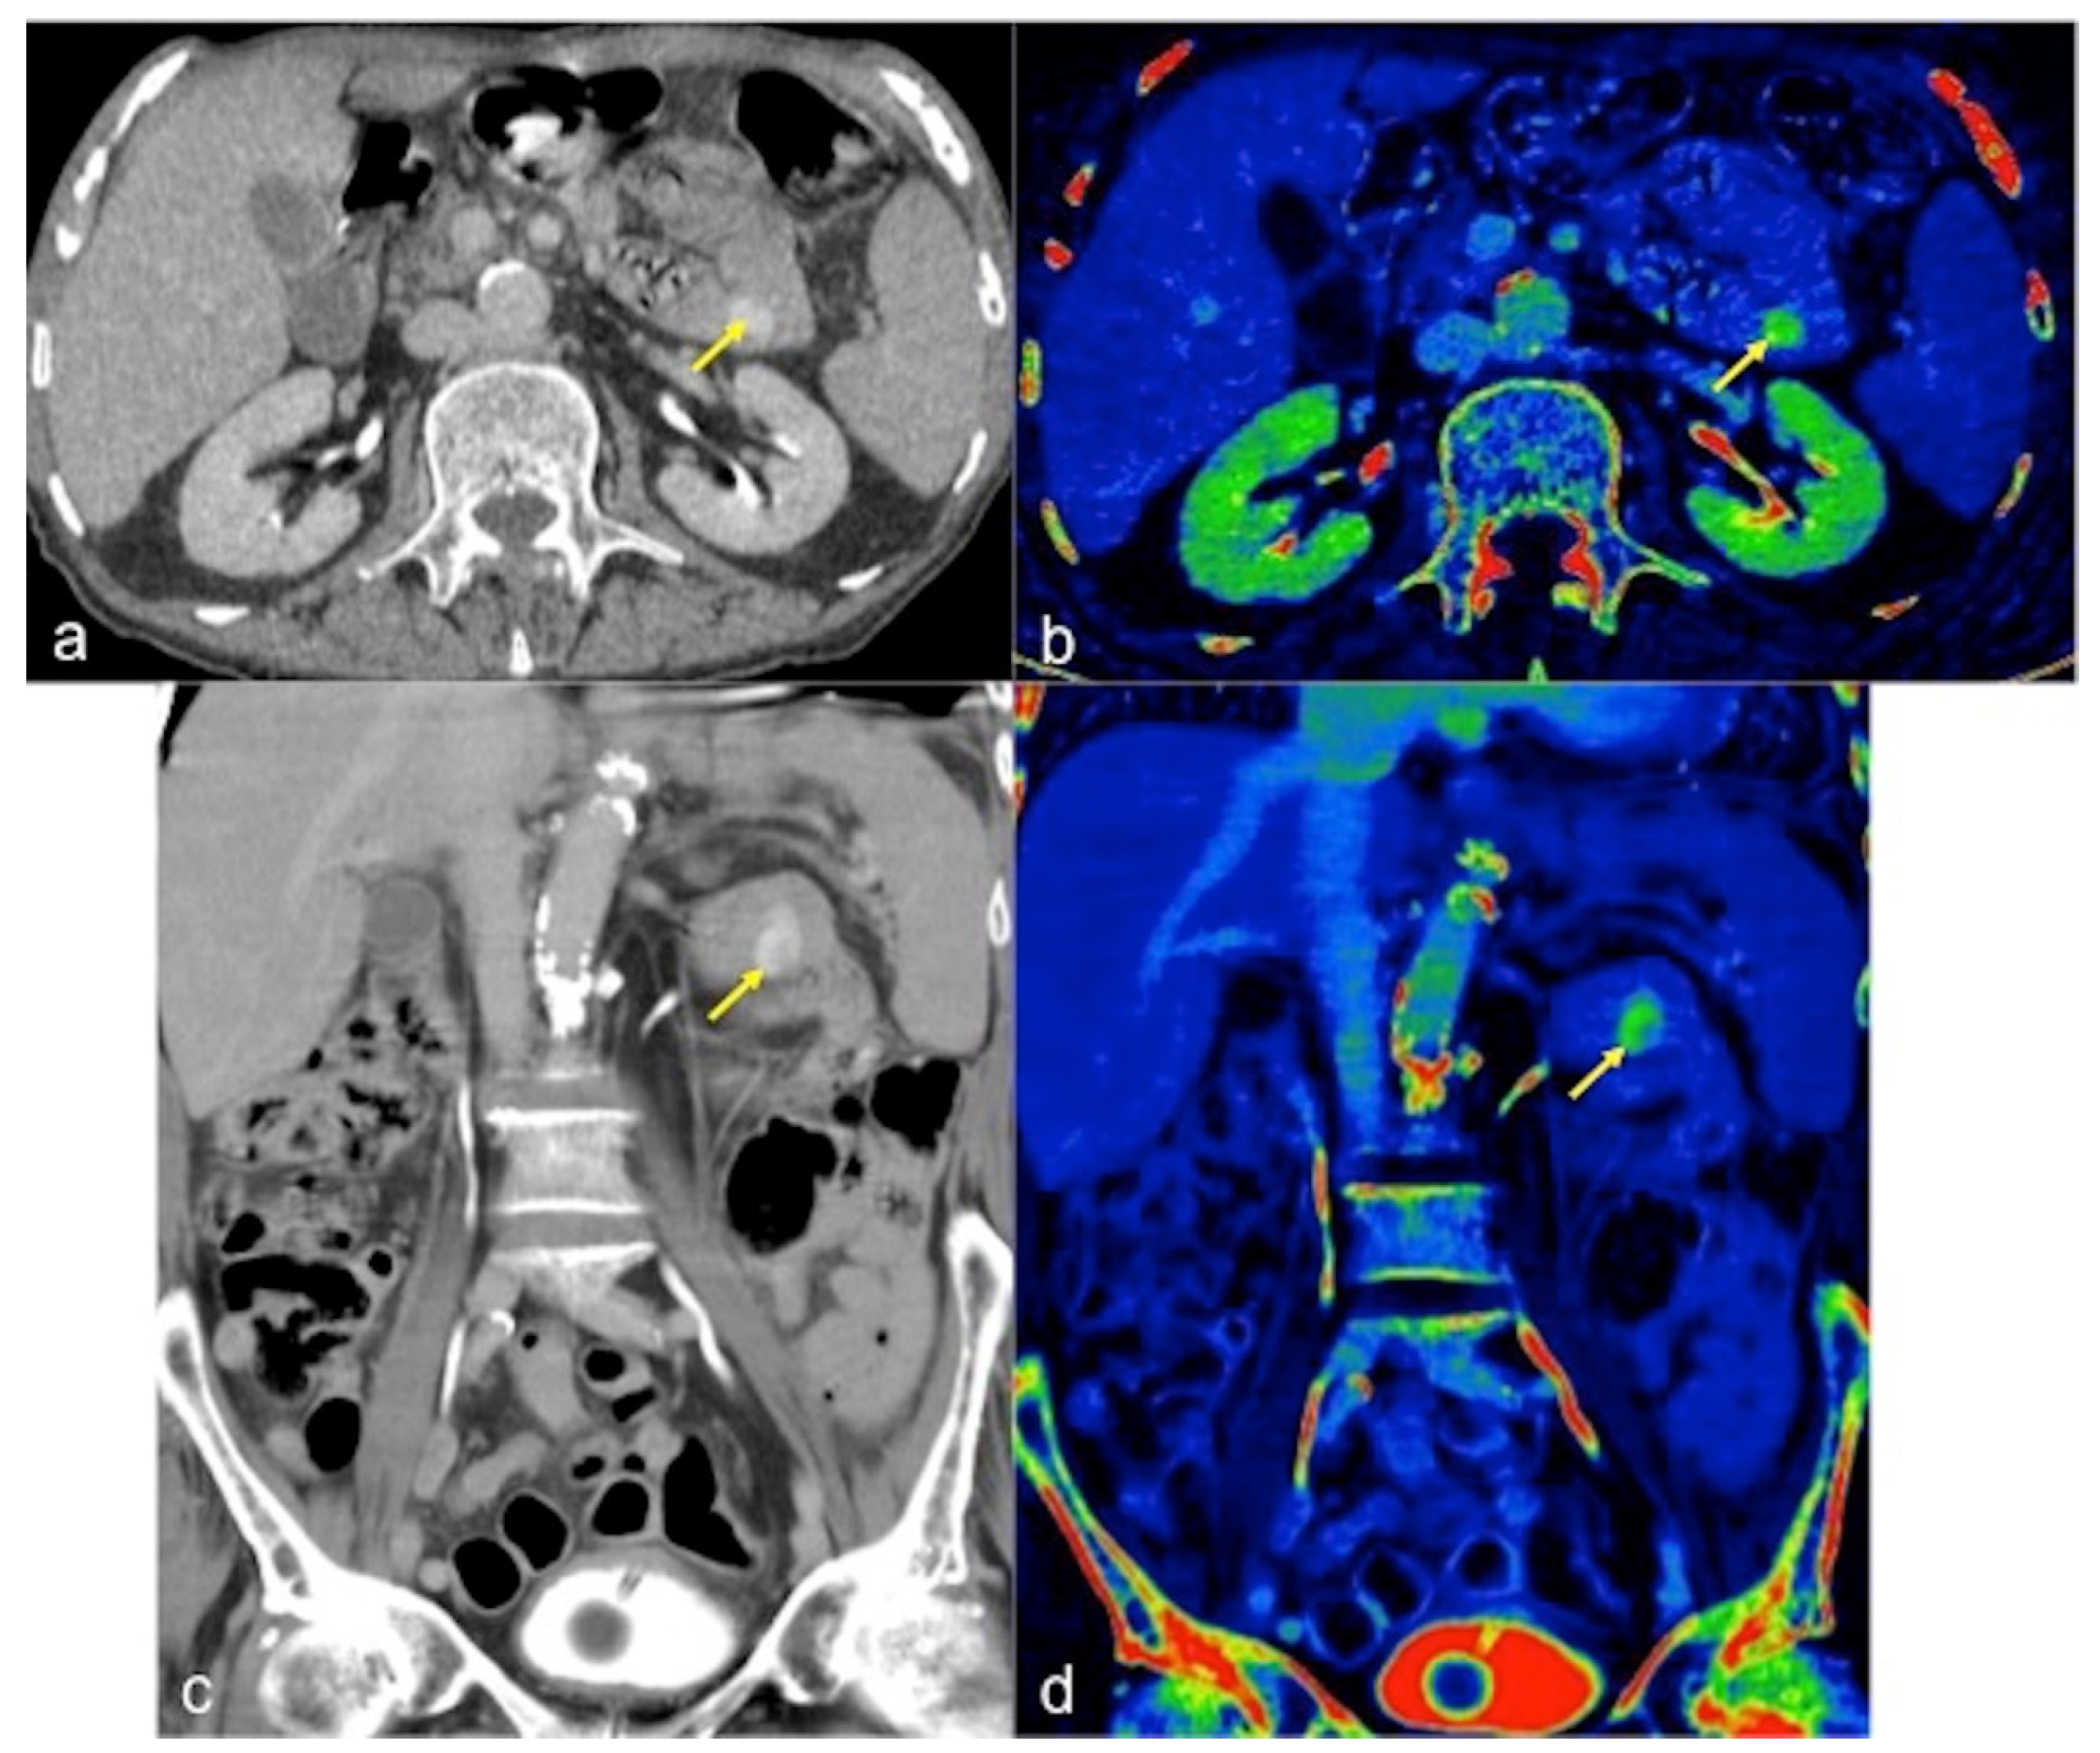

| Angiodysplasia (Figure 11) | Obscure bleeding. | Abnormally dilated, tortuous, thin-walled vessels involving small capillaries, veins and arteries. |